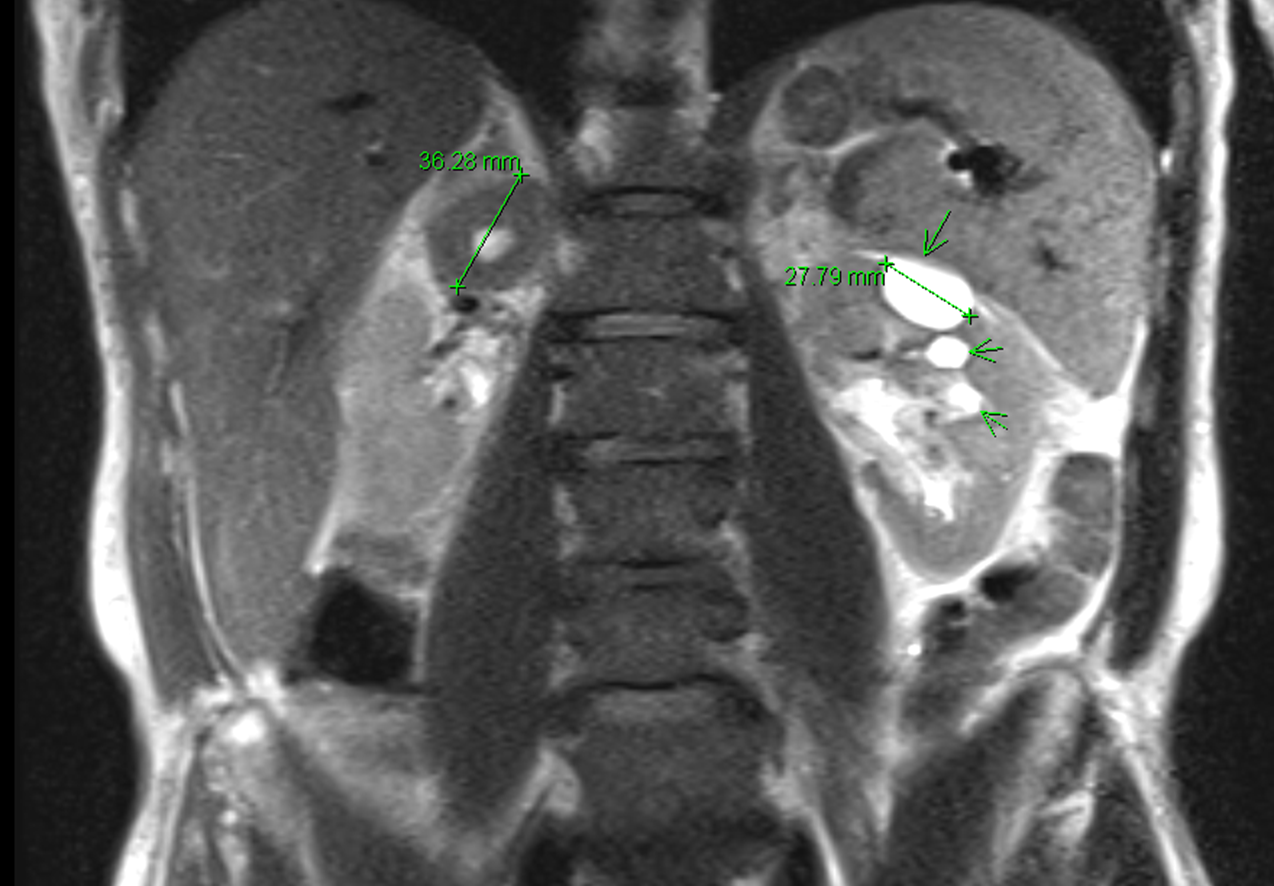

The CT scan revealed a 5 x 2.2 cm mass lesion in the right renal/suprarenal region inseparable from the kidney and the right adrenal gland and the differential diagnosis was either a RCC or adrenal carcinoma. He then proceeded to an MRI abdomen.

This again showed a mass in the right suprarenal region, inseparable from the right kidney and adrenal gland with some central necrosis. At this point, the decision was made to proceed with a partial nephrectomy for likely carcinoma.

One final image: on the MRI scan, he was incidentally found to have multiple gallstones – I just thought that the picture looked really cool.